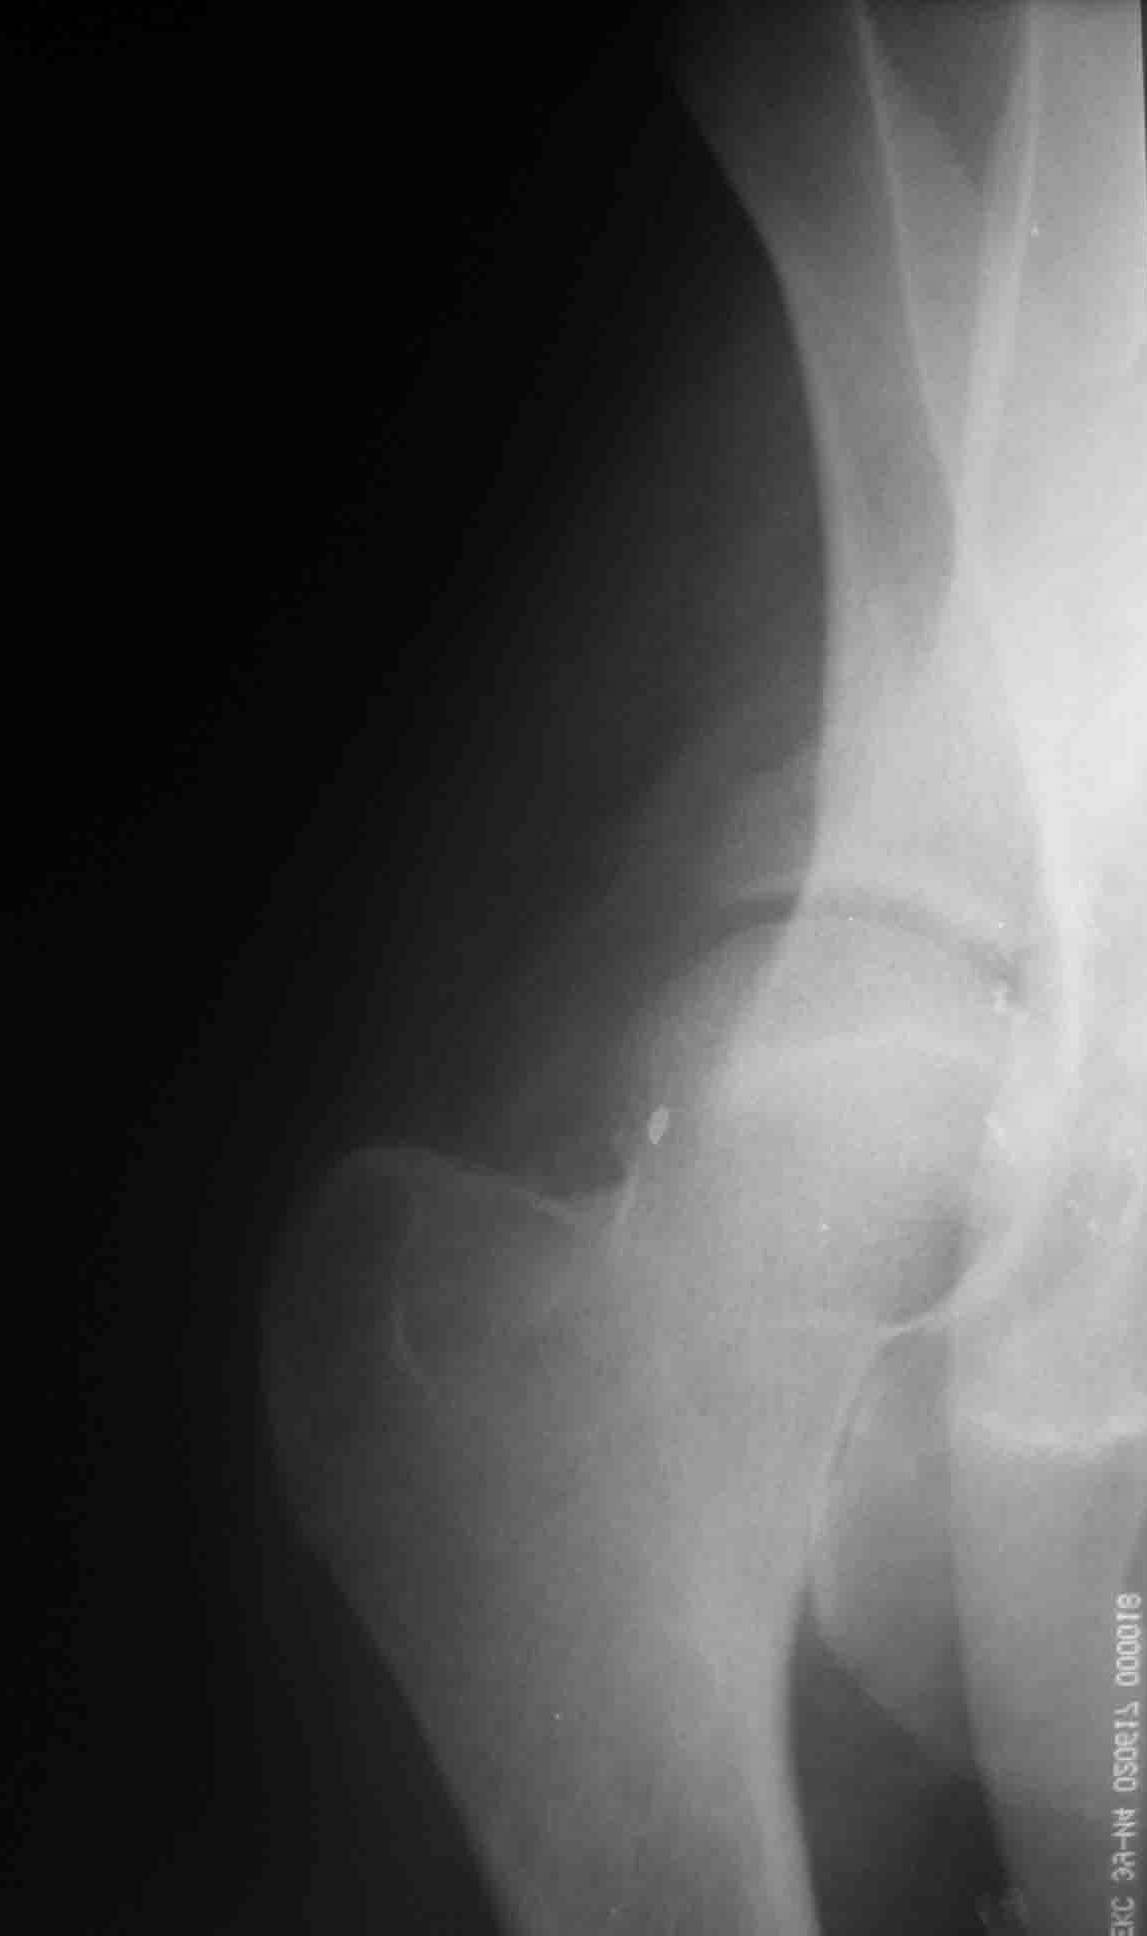

Молоодой человек 20 лет,задний вывих правого бедра, поперечный перелом и перелом заднего края правой вертлужной впадины. Самое сложное то, что после травмы уже прошло 8 недель. Планируем ввыполнить остеосинтез из двух доступов (задне-боковой и подвздошно-бедренный). Если у кого есть опыт остеосинтеза впадины из двух доступов посоветуйте с какого лучше начинать в данной ситуации.